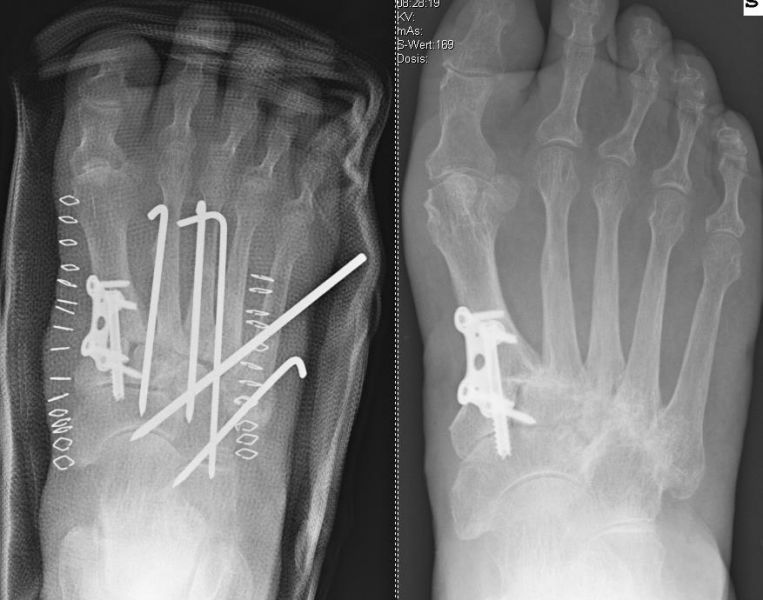

Es kommen verschiedene technische Möglichkeiten der operativen Versorgung in Frage.  Verwendung finden vor allem winkelstabile Plattensysteme, Schraubenosteosynthesen, Klammern, intraossäre Nagelsysteme, temporäre Kirschnerdraht-Transfixationen, Einbolzen von trikortikalem Span und Anlagerung von Spongiosa aus dem Beckenkamm oder dem Tibiakopf  (Abb. 2 und 3).

Durch die Arthrodese soll, wie oben beschrieben, eine Schmerzreduktion, eine Wiederherstellung der Fußstabilität und eine Korrektur der Fußstellung erreicht werden. Hierbei gibt es unterschiedliche Ansätze. Einige Autoren versteifen stets die mediale und laterale Säule bei TMT-Arthrosen 22. Andere Autoren sind der Meinung, dass nur die mediale Säule versteift werden sollte 18. Andere wiederum dehnen den Eingriff aus und beziehen die Cuneiforme-Gelenke mit in die Lisfranc-Arthrodese ein 21. Grundsätzlich zeigt sich der Trend, dass nur isoliert die arthrotischen und symptomatischen Gelenke versteift werden, ferner die Zugangswege klein und die Resektionsflächen der einzelnen Gelenke nur bis zur subchondralen Spongiosa eröffnet werden 23.